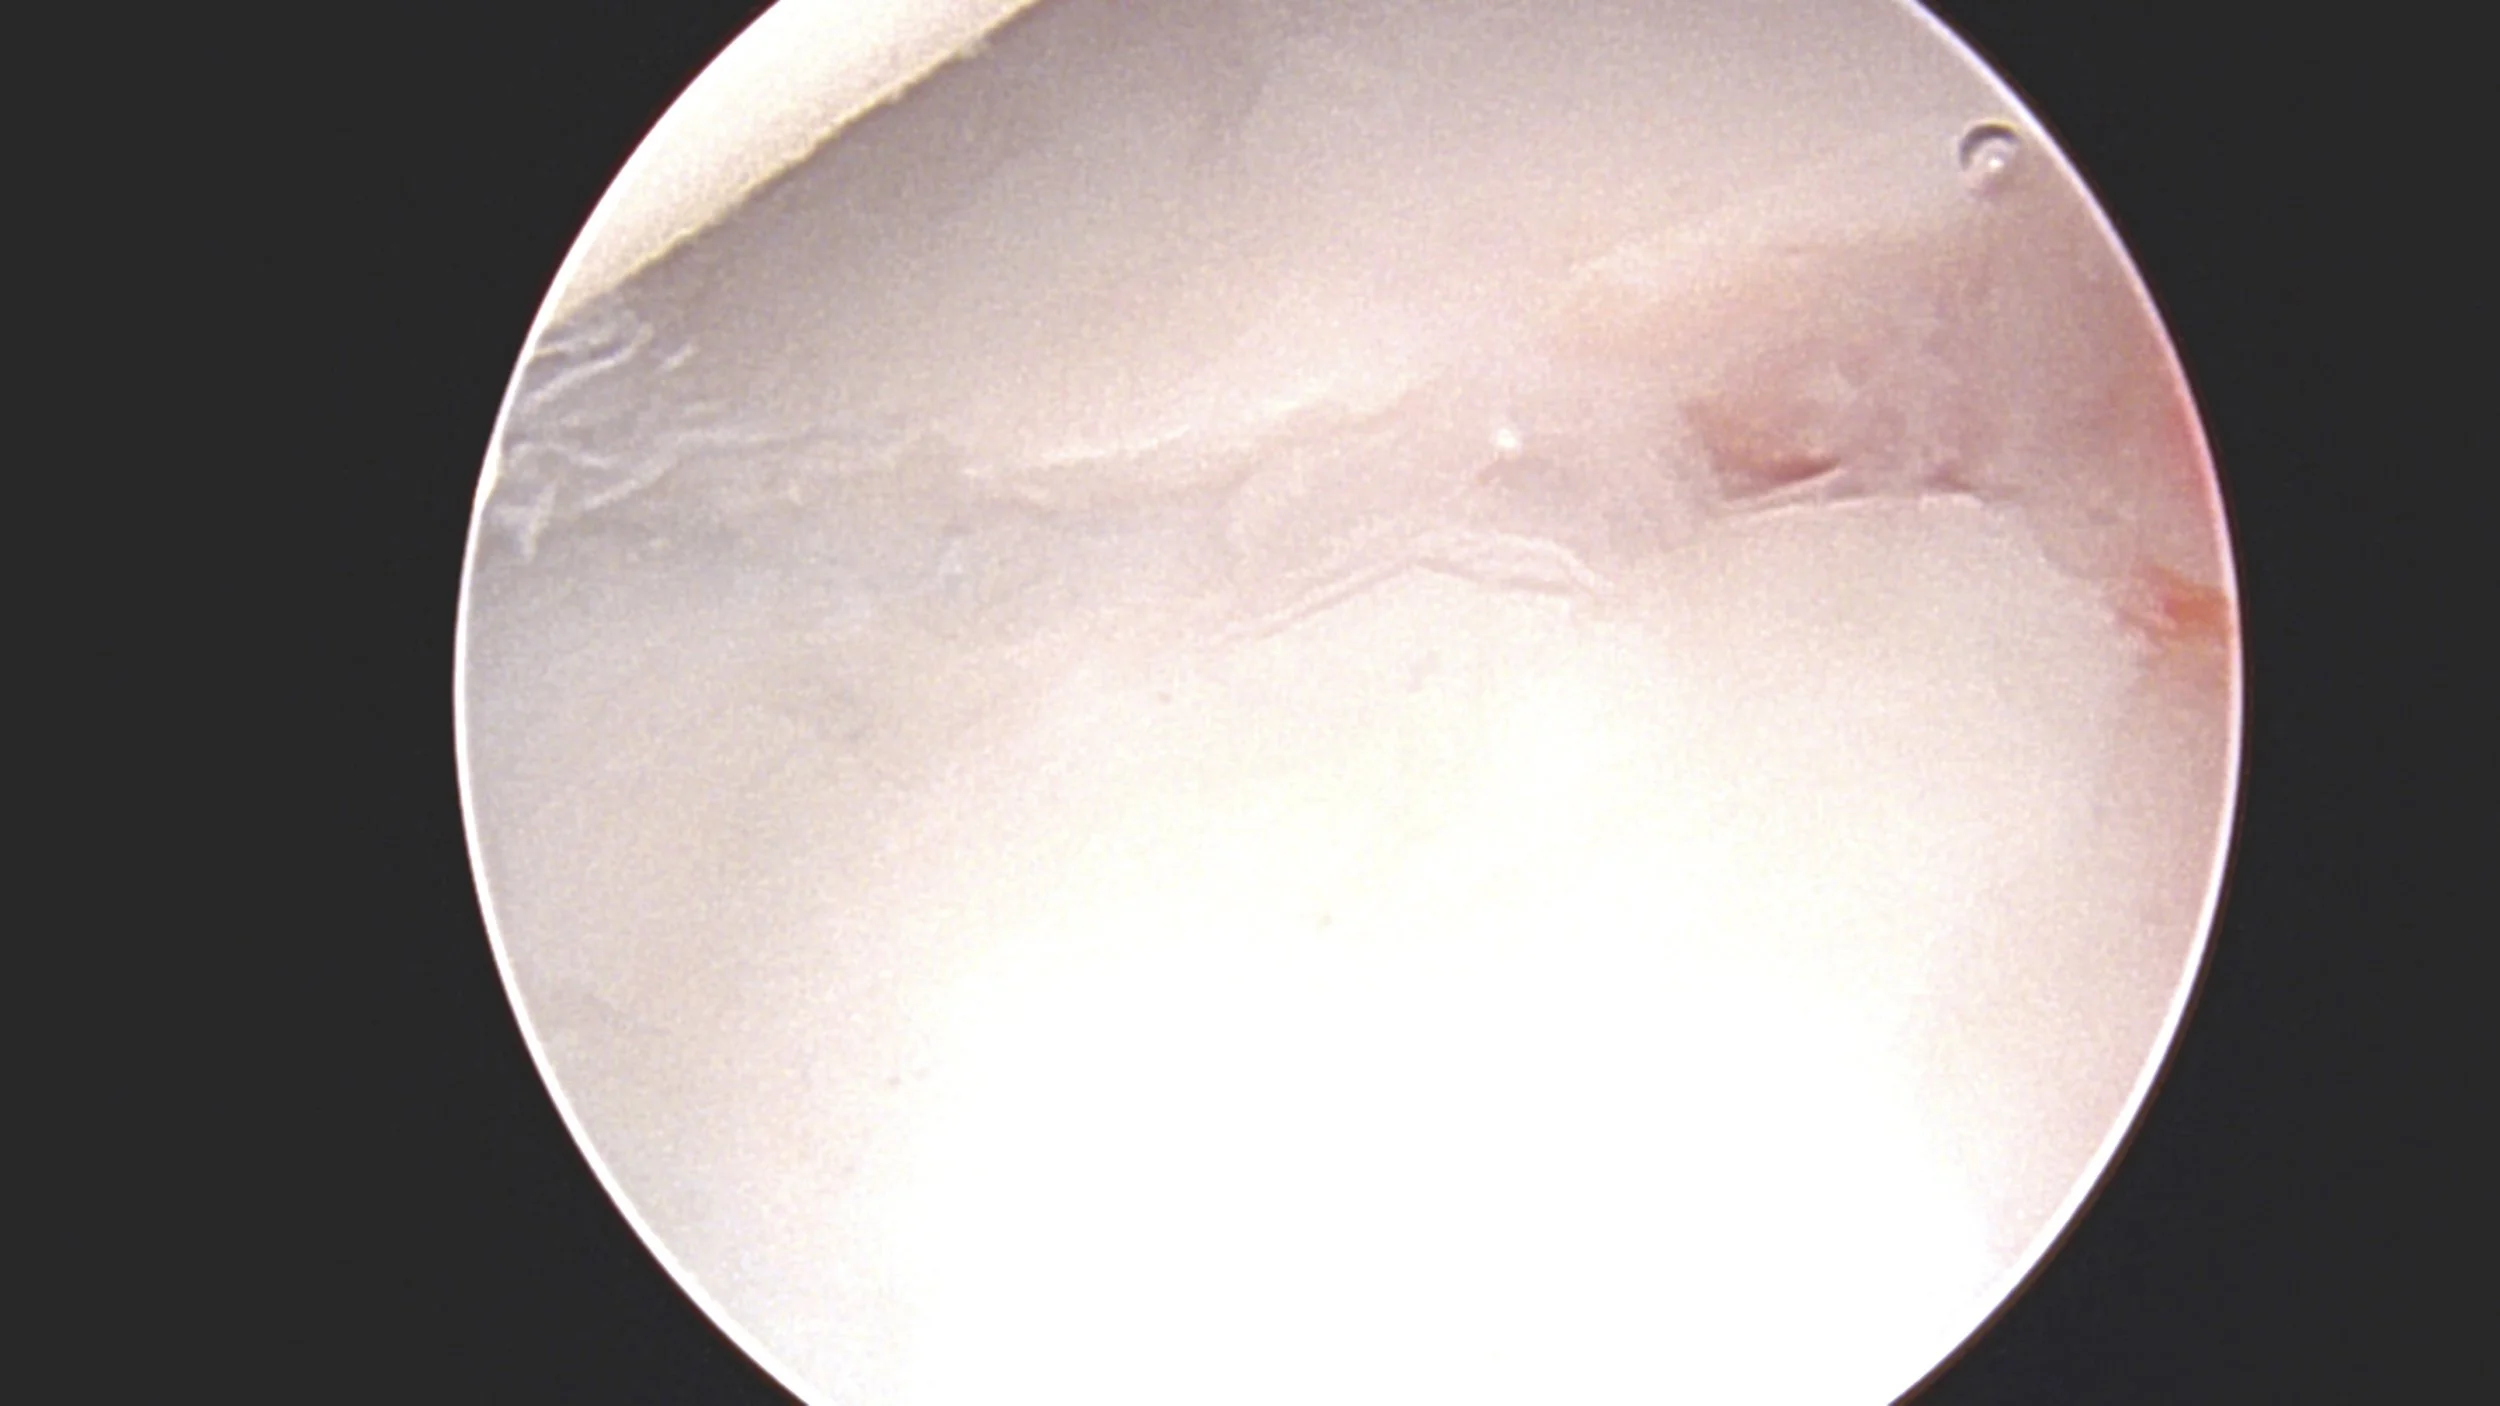

Distal radius fractures ( broken wrist) that has damaged the joint surface can be aided by arthroscopy to make the joint surface smooth.

Using wrist arthroscopic keyhole surgery to put the joint surface back in place